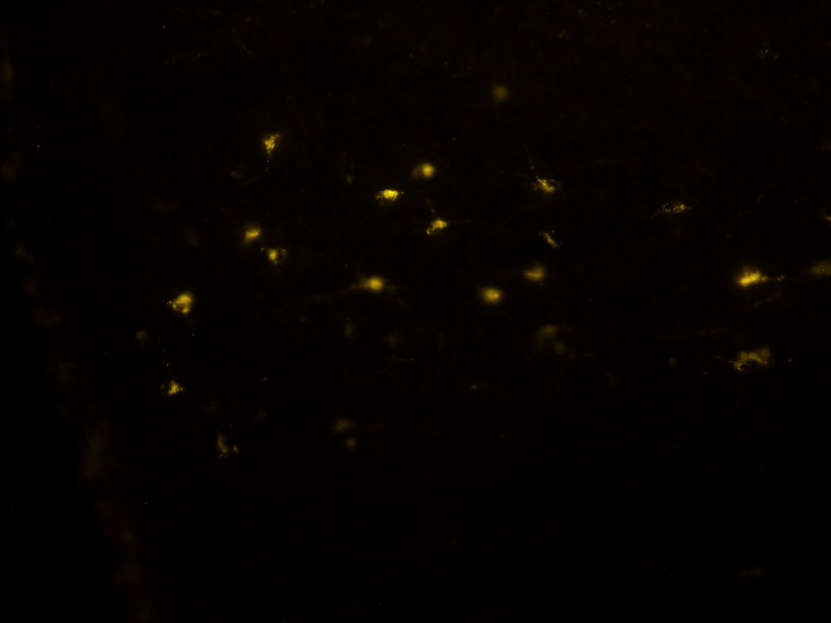

(c) Yellow image example

(f) Yellow mask example

Figure 2: Data preview. The figures show examples of fluorescence micrscopy pictures (Figures 2(a), 2(b) and 2(c)) and the corresponding ground-truth binary masks (Figures 2(d), 2(e) and 2(f)).

In contrast, the yellow collection (cf. Figure 2(c)) utilized staining for the b-subunit of Cholera Toxin (CTb). This monosynaptic retrograde neuronal tracer migrates within the soma and axons of neuronal cells projecting to the brain area where CTb was previously injected during in vivo experiments[19]. Consequently, this staining technique facilitates the identification of morphological connections between different brain regions.

Peculiar traits

In all image collections, the visual representation is characterized by the prevalence of two distinct color tones, which result from the deliberate selection of a specific wavelength. One tone appears darker, indicating areas where light has been filtered out, while the other tone is brighter and more intense, emitted by the fluorophore corresponding to the color of each collection (see Figures 2(a), 2(b) and 2(c)). As a result, the images can generally be depicted using variations of a single color. Consequently, a 1-D representation may be sufficient, or an alternative color space other than RGB could provide more informative and less redundant data.